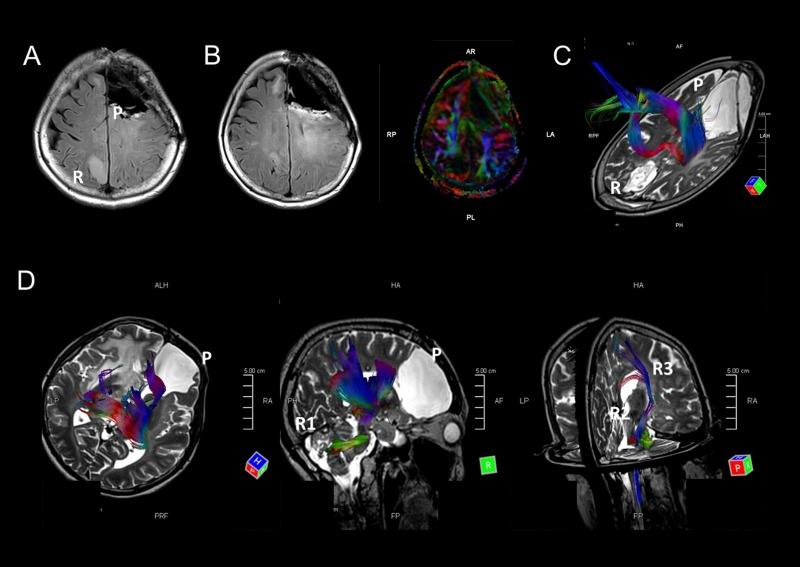

Most mutant gliomas harbor either 1p/19q co-deletions or mutation; 1p/19q co-deleted tumors have significantly better prognoses than tumors harboring mutations. To investigate the clinical factors that contribute to differences in tumor progression of mutant gliomas, we classified recurrent tumor patterns based on MRI and correlated these patterns with their genomic characterization. Accordingly, in mutant gliomas ( = 66), 1p/19 co-deleted gliomas only recurred locally, whereas mutant gliomas recurred both locally and in remote intracranial regions. In addition, diffuse tensor imaging suggested that remote intracranial recurrence in the astrocytomas, IDH-mutant with mutations may occur along major fiber bundles. Remotely recurrent tumors resulted in a higher mortality and significantly harbored an 8q gain; astrocytomas with an 8q gain resulted in significantly shorter overall survival than those without an 8q gain. OncoScan arrays and next-generation sequencing revealed specific 8q regions (i.e., between 8q22 and 8q24) show a high copy number. In conclusion, only tumors with mutations showed patterns of remote recurrence in mutant gliomas. Furthermore, an 8q gain was significantly associated with remote intracranial recurrence and can be considered a poor prognostic factor in astrocytomas, IDH-mutant.

大多数突变型胶质瘤存在1p/19q共缺失或突变;1p/19q共缺失的肿瘤预后明显优于携带突变的肿瘤。为了研究导致突变型胶质瘤肿瘤进展差异的临床因素,我们根据磁共振成像(MRI)对复发性肿瘤模式进行分类,并将这些模式与其基因组特征相关联。因此,在66例突变型胶质瘤中,1p/19共缺失的胶质瘤仅局部复发,而携带突变的突变型胶质瘤则在局部和颅内远处区域复发。此外,弥散张量成像表明,伴有突变的异柠檬酸脱氢酶(IDH)突变型星形细胞瘤的颅内远处复发可能沿主要纤维束发生。远处复发性肿瘤导致更高的死亡率,且明显存在8号染色体长臂(8q)增益;有8q增益的星形细胞瘤的总生存期明显短于无8q增益的星形细胞瘤。OncoScan阵列和下一代测序显示特定的8q区域(即8q22和8q24之间)显示出高拷贝数。总之,在突变型胶质瘤中,只有携带突变的肿瘤表现出远处复发模式。此外,8q增益与颅内远处复发显著相关,可被视为IDH突变型星形细胞瘤的不良预后因素。